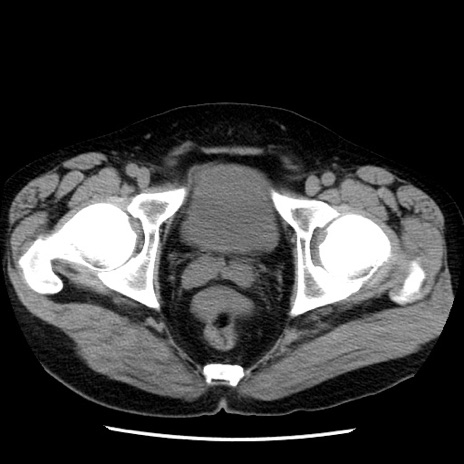

症例29(横断像)

【症例】40歳代男性

【現病歴】2日前から胃痛あり。徐々に周期的な激痛に変化した。本日になっても激痛があるため受診。

【身体所見】意識清明、BT 38-39℃台あり、腹部:膨満、やや硬、右下腹部に圧痛あり。

【データ】WBC 8500、CRP 23.26